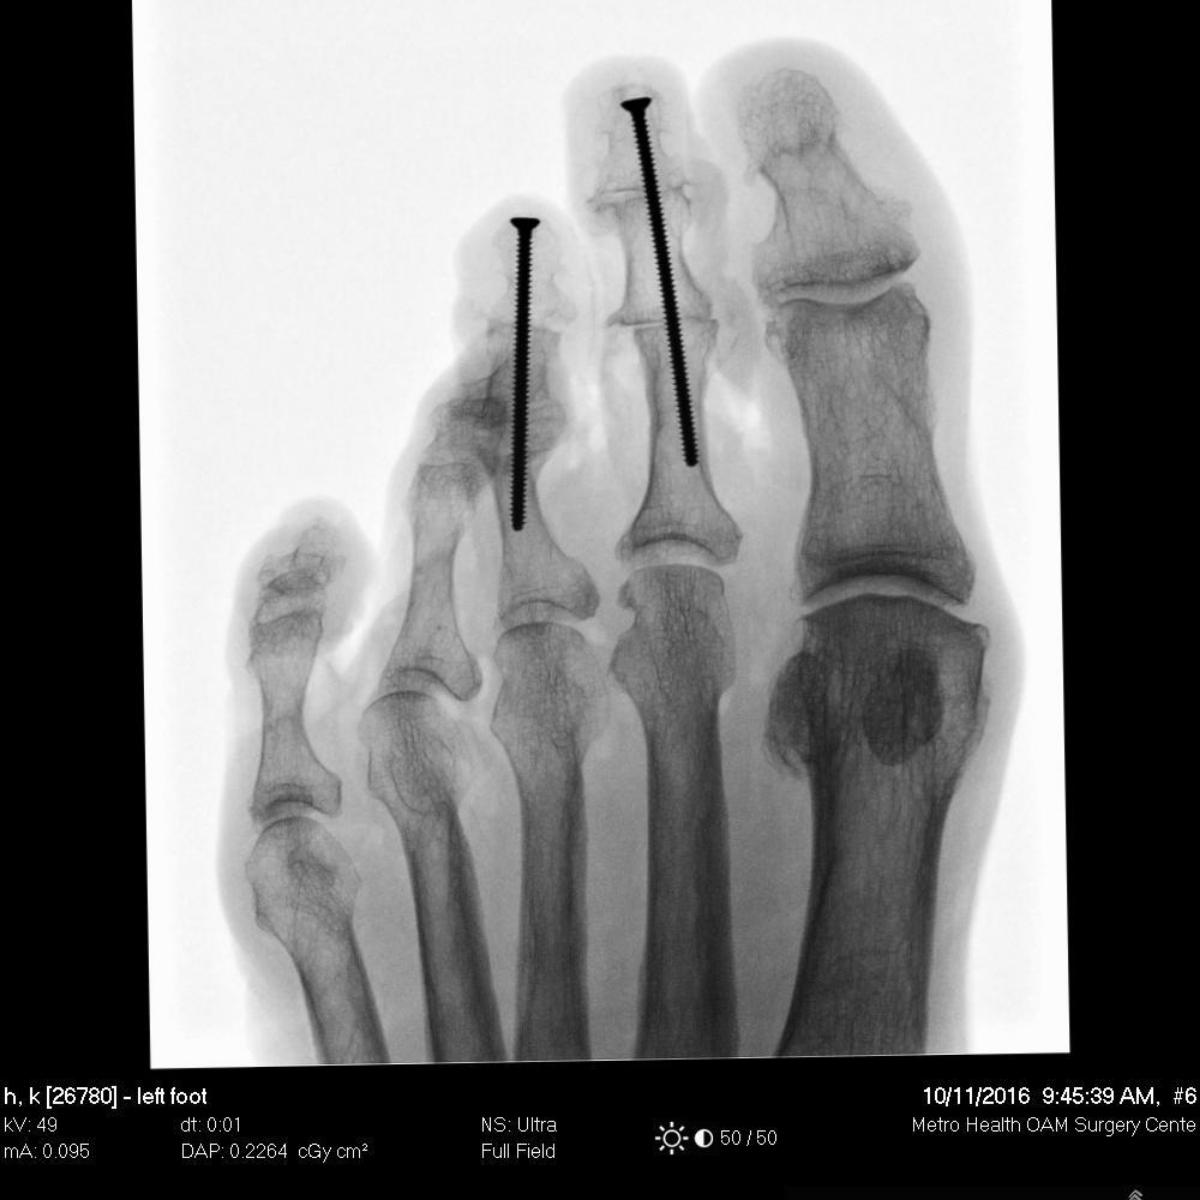

Clinical Images

Image quality to rival standard X-ray

- Image processing algorithms deliver superb distortion-free image quality.

- System allows larger anatomy imaging with dose optimization.

- Automatic imaging with dose optimization for all extremity imaging.